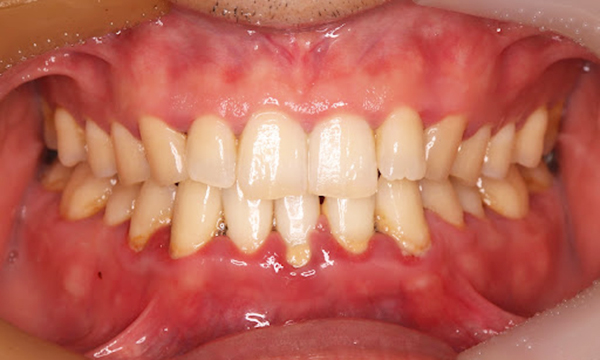

重度歯周病

特徴

歯周炎の段階です。

• 歯がグラつく、抜け落ちそう

• 歯ぐきからの出血が長期間、またはずっと続く

• 歯ぐきから膿がでる

• 口臭が強い

• 歯ぐきが下がって歯と歯の隙間が目立つ

重度歯周病の歯ぐきの写真

歯科医院でのクリーニング、歯ぐきを切開しておこなう歯石除去や歯の骨を補填する手術などあらゆる治療方法を用いて治療をおこないます。歯を残すことは前提ですが、リスクになりうる歯を抜歯するご相談をおこなうこともあります。

グラグラになった歯にブラシの毛先を当て磨くことは簡単ではありません。また歯ぐきの中に入り込んだ汚れは歯ブラシで取りきることができないため歯科医院での歯周病治療、クリーニングを受けるようにしましょう。